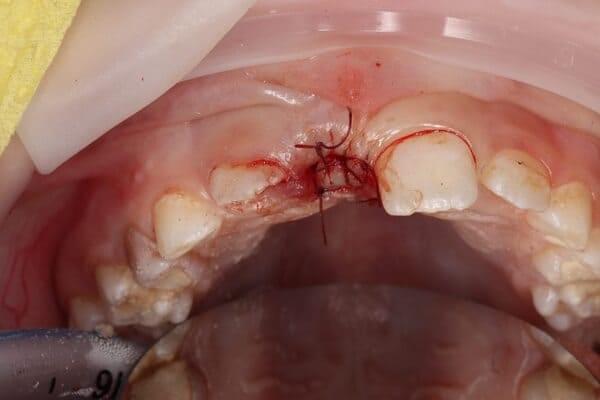

Травма постійних зубів. Олег Ковнацький.

Дівчинка 7 років, перше вересня, гойдалка… Вивих постійного зуба: якщо в такій ситуації зволікати, дитина може втрати постійний зуб назавжди. Батькам порекомендували нас і пацієнти одразу приїхали. Через складність і травматичність процедур вирішено проводити лікування в анестезіологічному супроводі. Зуб поставлений на місце (репонований), проведена хірургічна обробка і ушивання рани губи. Останнє фото через рік після травми: зуб на місці і корінь продовжує розвиватись, губа повністю загоїлась